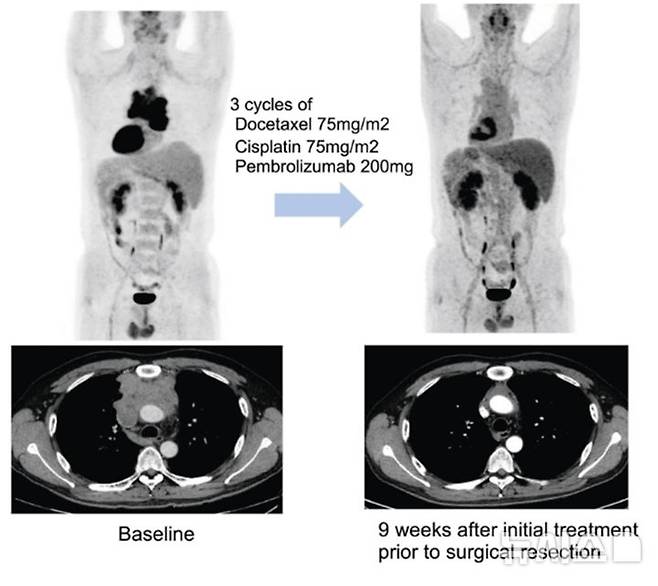

연구팀은 이들 환자에게 3주 간격으로 세 번에 걸쳐 기존 항암화학요법에 펨브롤리주맙을 병용 투여한 다음 수술 가능 여부를 평가했다.

연구팀에 따르면 추적관찰 기간 27.5개월(중앙값) 동안 전체 환자의 57.5%(23명)에서 수술 전 치료를 통해 종양의 크기가 유의미하게 감소하는 반응을 보였다. 또 82.5% 환자에서는 해당 치료로 인해 질병의 진행이 억제 되는 질병 조절이 관찰됐다.